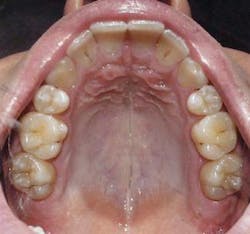

Mount and Hume have devised a system for caries classification.9-12 The chart in Figure 3 would allow the practitioner to rate caries by location (or size site) and degree of caries involvement.

There are only three locations for decay on a tooth surface:

1 Pits and and fissures

2 Contact areas

3 Cervical areas

As caries progresses in these areas, the size of the surgical intervention will increase. Sizes of decay would be:

1 Initial lesion, with possible medical intervention

2 Decay beyond remineralization

3 Decay undermining cusp or possible cusp fracture due to decay

4 Loss of cusp or incisal edge

Each classification has a corresponding different approach to cavity preparation. Mount has provided an excellent description in his paper published in Operative Dentistry.12